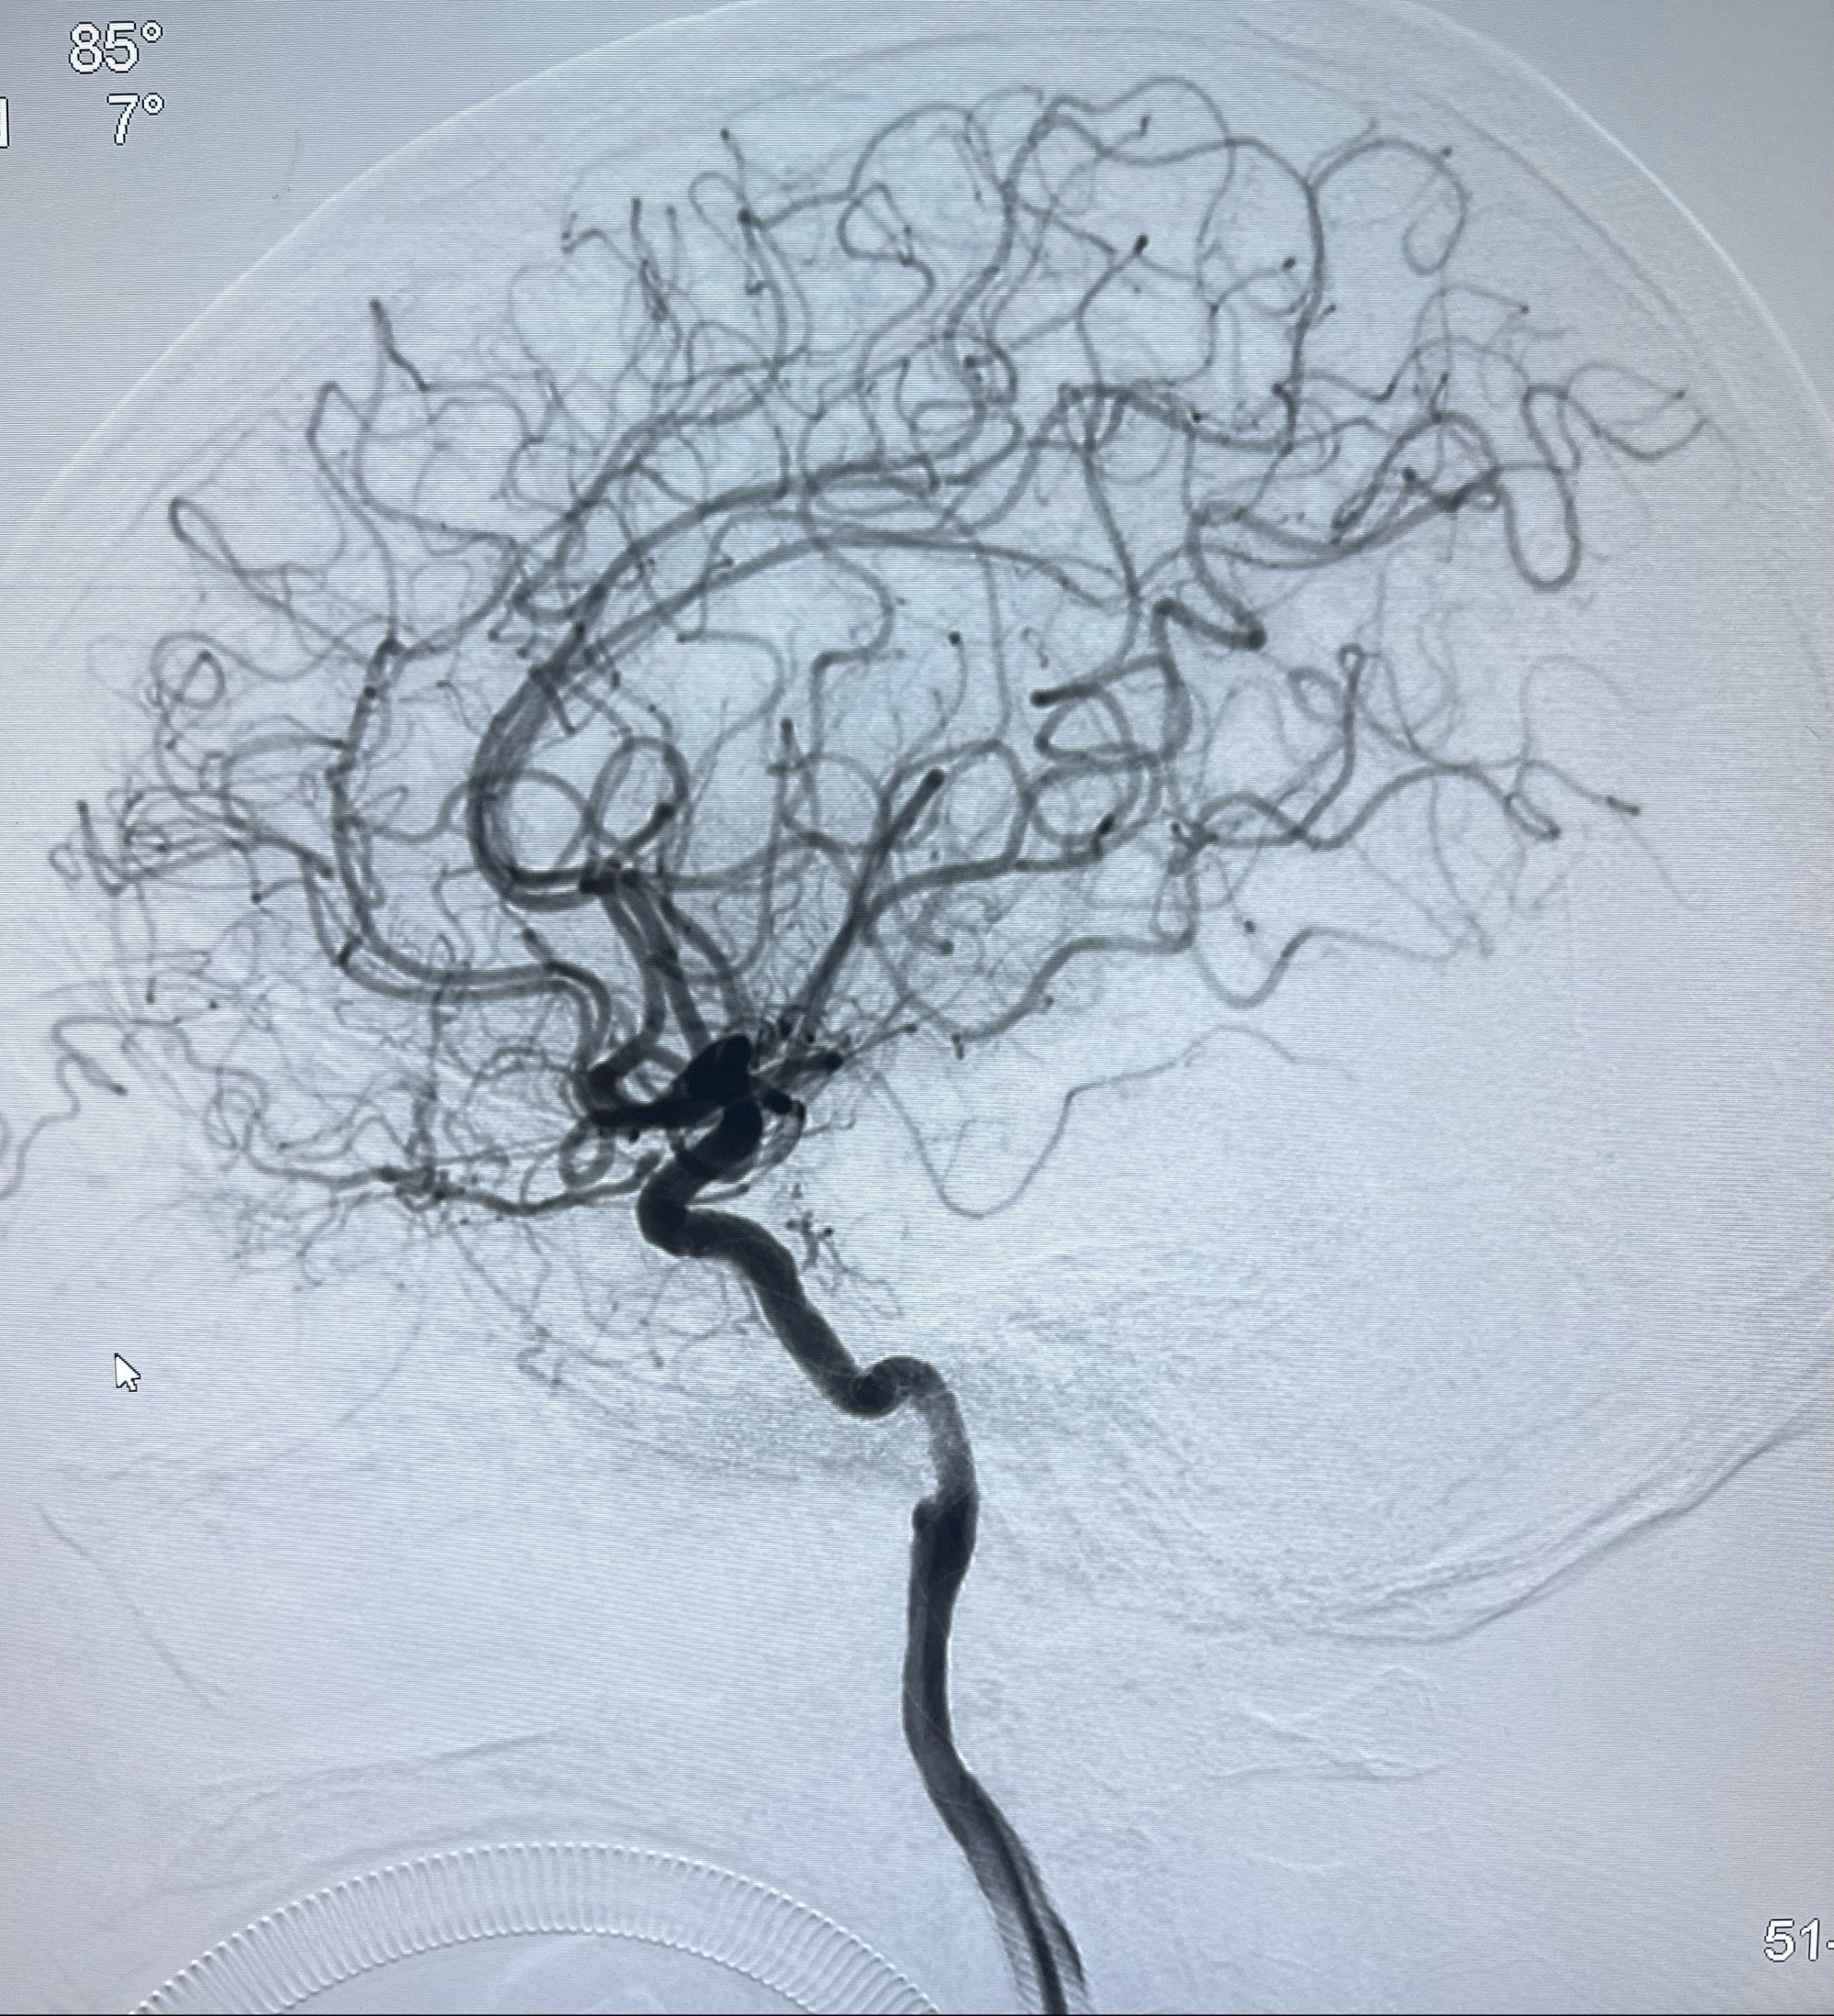

双抗准备后于2023-07-13在全麻下行右侧颈内动脉功能保护

麻醉苏醒佳,遵嘱活动!

术后给予替罗非班300ug/h维持,序贯阿司匹林100mg➕泰嘉75mg口服